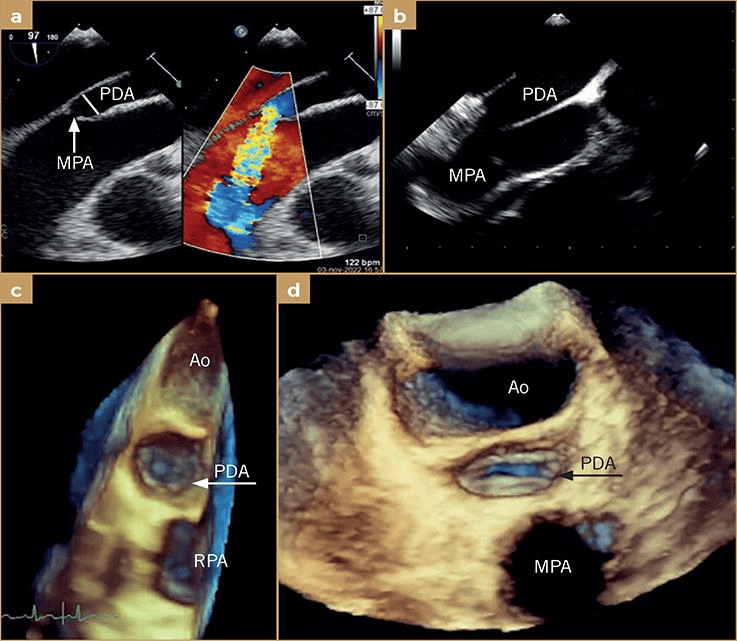

a) 经食管超声心动图(tee),带和不带彩色多普勒,2b型,指状动脉导管未

图片尺寸737x641